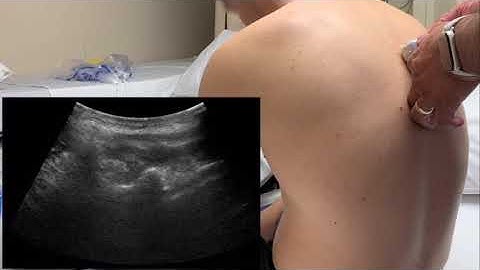

VAA Video Abstract No 2, April 2021 - Transversal approach for the lumbar erector spine plane block